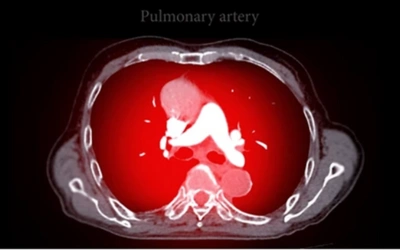

CT Pulmonary Angiography (CTPA):

Used in evaluating pulmonary diseases that may lead to PH, such as blood clots or other pulmonary diseases.